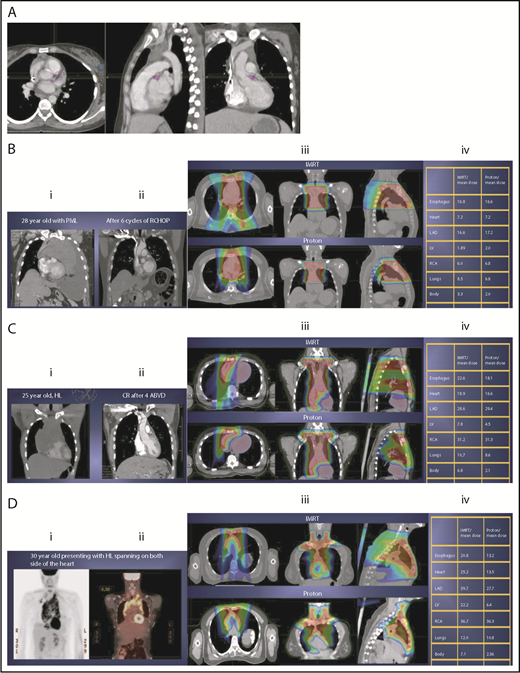

Scenario 1: mediastinal target is completely above the heart with no axillary involvement

The take-off of the left main stem coronary artery is used to define whether the target is above or below the heart (Figure 2A). In this example (Figure 2B), the exposure of the heart is quite comparable, regardless of which technique is used. Differences in DVHs, as well as the mean dose to other structures, are similar to the proton and IMRT plans.

Three scenarios of the relation between mediastinal disease and the heart. (A) Showing how to use the takeoff of the left main stem coronary artery (outlined in pink) to determine the upper and lower mediastinal locations. (B) Scenario 1: coronal CT images of a 28-year-old man with primary mediastinal lymphoma before (i) and after (ii) 6 cycles of rituximab, cyclophosphamide, doxorubicin, vincristine, prednisone (RCHOP) chemotherapy presenting for consolidation with radiation. (Biii) Axial, coronal, and sagittal views of an IMRT plan (upper panels) and a proton plan (lower panels). (Biv) Corresponding mean doses to critical structures using IMRT vs protons. (C) Scenario 2: coronal CT images of a 25-year-old man with Hodgkin lymphoma before (i) and after (ii) 4 cycles of doxorubicin, bleomycin, vinblastine, and dacarbazine (ABVD) chemotherapy presenting for consolidation with radiation. (Ciii) Axial, coronal, and sagittal views of an IMRT plan (upper panels) and a proton plan (lower panels). (Civ) Corresponding mean doses to critical structures using IMRT vs protons. (D) Scenario 3: coronal CT images of a 30-year-old man with recurrent Hodgkin lymphoma as shown in the coronal images of a PET/CT scan (i-ii) presenting for definitive radiation. (Diii) Axial, coronal, and sagittal views of an IMRT plan (upper panels) and a proton plan (lower panels). (Div) Corresponding mean doses to critical structures using IMRT vs protons.

Scenario 2: target spans the right side of the heart

For the targets on the right side of the heart, IMRT often provide comparable doses to the heart and other structures as proton therapy. Notably, however, even when proton plans give a dosimetric advantage over IMRT plans, the magnitude of advantage could vary between cases, and it needs to be judged individually. For example, for the patient shown in Figure 2C, the mean doses to critical structures from proton therapy are sufficiently lower than those from IMRT to suggest that proton therapy may be preferred because of the large volume spanning the right side of the heart. This example illustrates the need for careful consideration of individual cases before deciding on treatment.

Scenario 3: target is on both sides of the heart

Disease that spans significantly in front of the heart anteriorly, posteriorly, or to the left side poses a particular challenge for IMRT; therefore, proton therapy may be the superior plan. Notably, toxicity to the heart and lungs is not eliminated by using proton therapy; rather, the dose to the heart may be lower than IMRT. Thus, for cases like in Figure 2D, clinicians should carefully weigh the therapeutic benefit against the long-term risks for radiation-induced treatment toxicities before deciding on which technique should be used. Indeed, in this case, proton therapy can significantly avoid the heart and should be sought in an attempt to reduce the dose to the heart substructures.